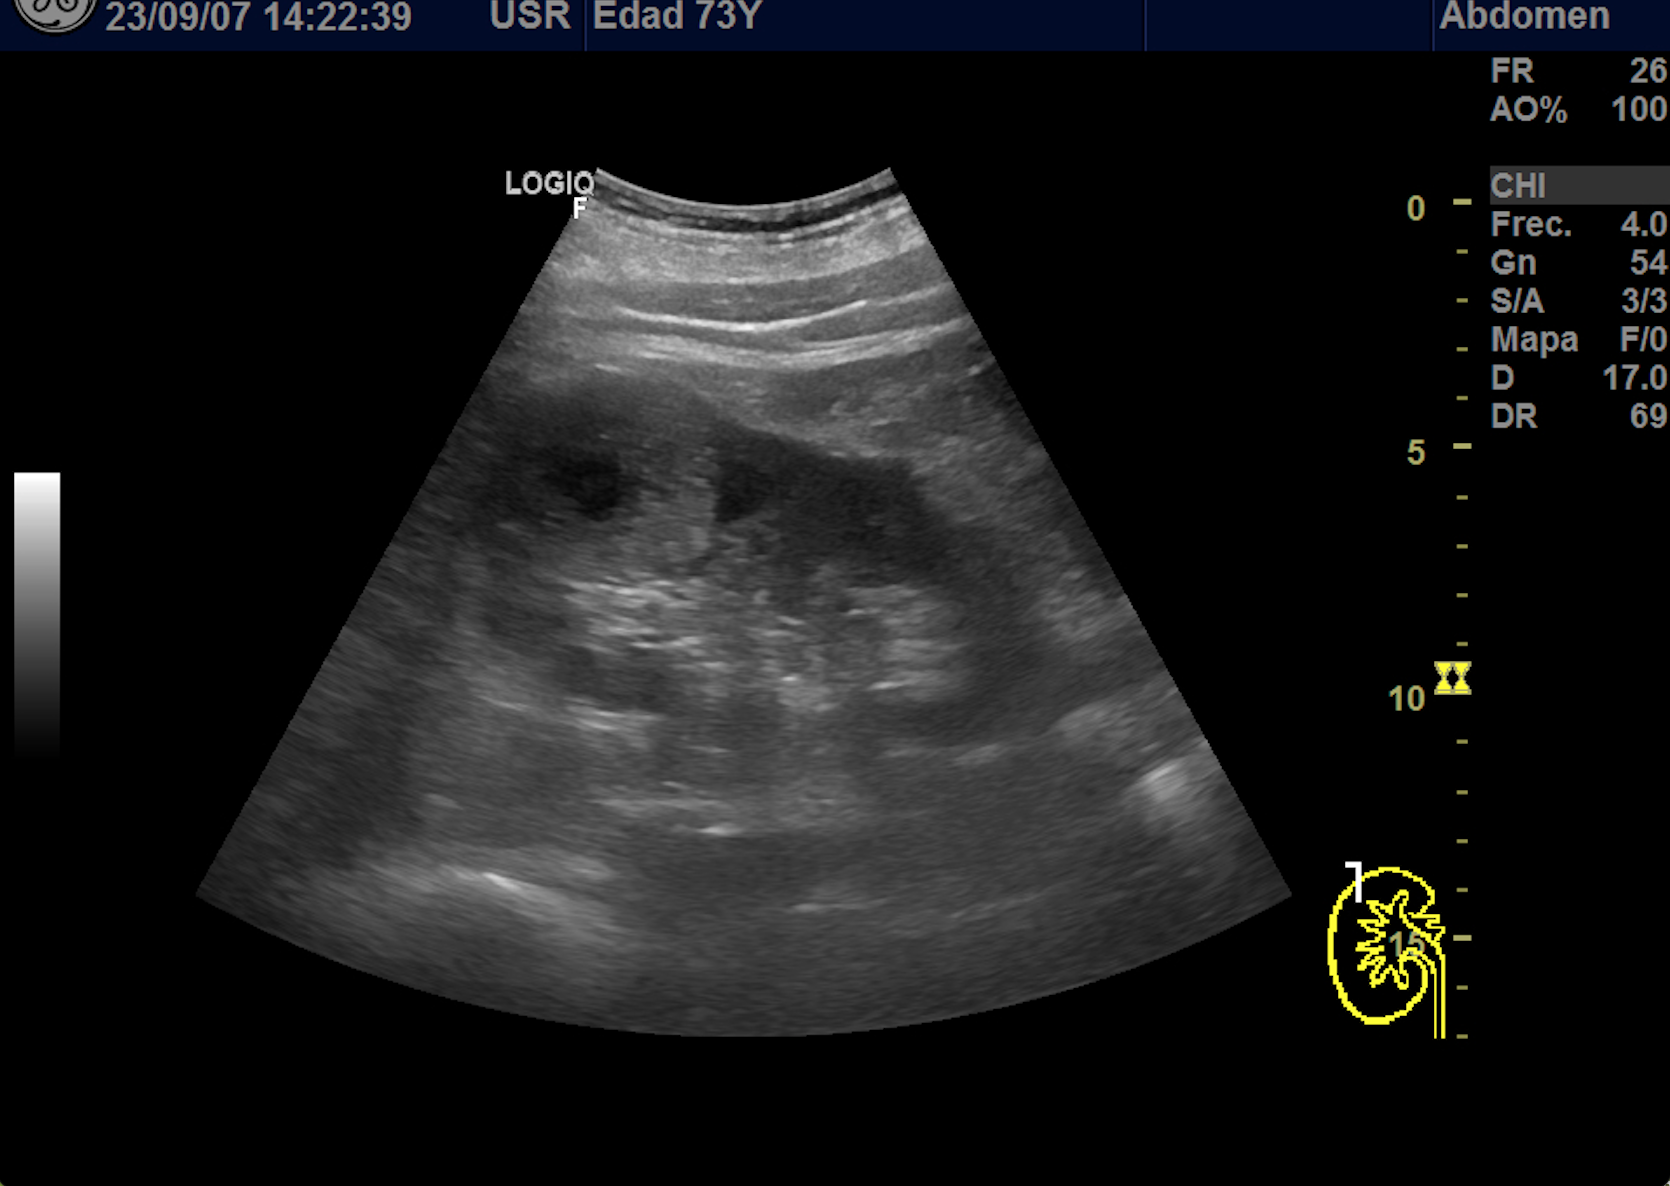

Hallazgos ecográficos

En polo superior de riñón derecho se observa una imagen redondeada, bien delimitada, isoecoica con un área central hipoecoica con vascularización periférica y central de 4,1 x 4,18 x 4,94 cm.

Riñon izquierdo sin hallazgos.